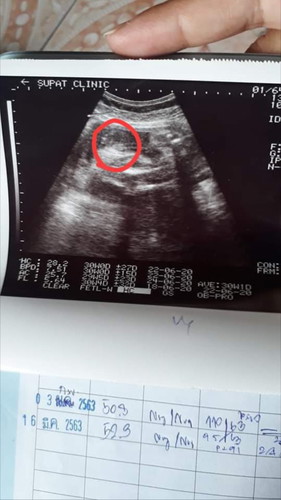

ช่วยดูเพศน้องหน่อยค่ะ

คุณหมอบอกว่า น่าจะ ผญ.80% แต่ยังไม่ฟันธง100% เพราะ น้องหนีบๆขาอยู่หน่อย กลัวอ้าออกมากแล้วปิกาจู้โผล่ แม่ๆท่านไหนพอดูออกบอกเราหน่อยค่ะว่าแบบนี้ไปทางไหนมากกว่ากันหรือมีภาพอัลตร้าซาวด์ ของลูกสาวหรือลูกชายเอามาแชร์บอกต่อบ้างนะคะ คุณหมอวงกลมมาให้ค่ะว่าตรงนั้นเป็นเพศ แต่น้องหนีบๆไว้